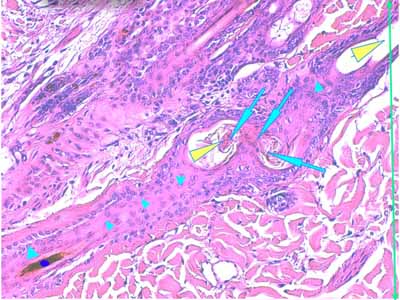

Photo 2 (Hémalun Eosine X 40) : biopsie réalisée en marge d’un ulcère.

L’épiderme, fragilisé, se détache artéfactuellement et se désolidarise du derme superficiel.

Le derme montre une plage cellulaire dense qui s’étend du derme superficiel jusqu’au derme profond.

En contact avec cette plage, se trouve un follicule pileux dont la tige pilaire est fragmentée

et circonvolutée dans son fourreau épithélial.

Légendes de la Photo 2 :

- Pointe de flèche orange : ulcère

- Ovale jaune : plage cellulaire inflammatoire s’étendant du derme superficiel au derme profond

- Flèche turquoise : follicule pileux dont la tige pilaire est fragmentée et circonvolutée dans son fourreau épithélial

- Flèches jaunes : épiderme fragilisé qui se détache du derme

- Double flèche orange : épaisseur épidermique

- Double flèche verte : épaisseur dermique

- Double flèche bleue : épaisseur hypodermique